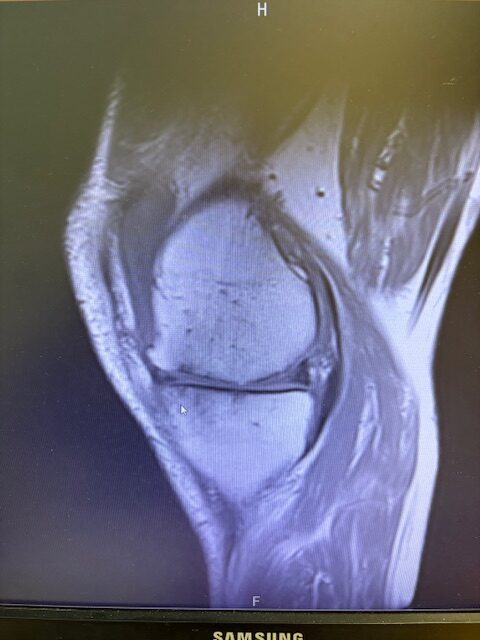

Ο ακτινολογικός έλεγχος (ακτινογραφίες/μαγνητική τομογραφία) ανέδειξε προχωρημένη οστεοαρθρίτιδα του έσω κονδύλου, με πλήρη διατήρηση του έξω διαμερίσματος και της επιγονατιδομηριαίας άρθρωσης. Με βάση αυτά τα ευρήματα, ο ασθενής ήταν ιδανικός υποψήφιος για μερική (μονοκονδυλική) αρθροπλαστική γόνατος.

Πραγματοποιήθηκε απεικόνιση και ψηφιακός σχεδιασμός της επέμβασης, ώστε να προσδιοριστεί με ακρίβεια το μέγεθος και η θέση των προθέσεων. Ο στόχος ήταν να αποκατασταθεί η φυσιολογική μηχανική του γόνατος, διατηρώντας ανέπαφα τα υγιή τμήματα της άρθρωσης, τους συνδέσμους και τους γύρω μυς.